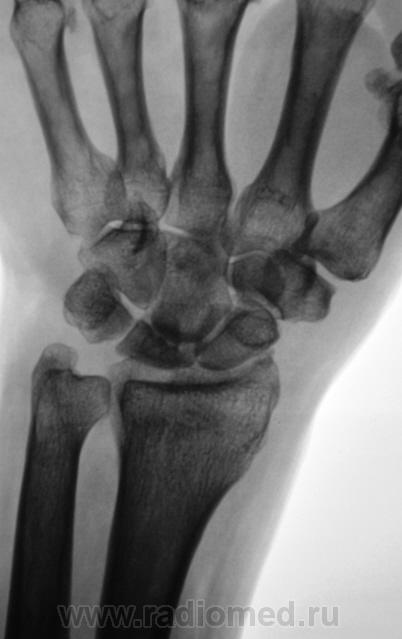

Пол пациента: Мужской пол Тип патологии: Другое Область исследования: Скелетно-мышечная система Методы исследования: Rg Пациент направлен на рентгенографию лучезапястного сустава с диагнозом - "Деформирующий артроз" Произведено стандартноы исследование. https://radiomed.ru/sites/default/files/styles/case_slider_image/public/user/12/2.DFA_..JPG?itok=Id8ocGkL ID:2136 Ср, 24/03/2010 - 18:38 #1 rentgengb1 Не на сайте Был на сайте: 11 лет 12 месяцев назад Зарегистрирован: 13.02.2009 - 23:02 Публикации: 290 Асептический некроз полулунной кости? Ср, 24/03/2010 - 19:04 #2 Катенёв Валенти... Не на сайте Был на сайте: 7 лет 3 недели назад Зарегистрирован: 22.03.2008 - 22:15 Публикации: 54876 Изображения с увеличением. Приложения: Ср, 24/03/2010 - 19:06 #3 DR.RAD Не на сайте Был на сайте: 11 лет 8 месяцев назад Зарегистрирован: 25.03.2009 - 18:22 Публикации: 805 и как следствие артроз лучезапястного сустваа... Пнд, 29/03/2010 - 00:03 #4 brainmodel Не на сайте Был на сайте: 2 месяцев 2 недели назад Зарегистрирован: 18.03.2010 - 22:04 Публикации: 2881 Болезнь Кинбека со вторичным артрозом, стадия фрагментации. Verum plus uno esse non potest.

Асептический некроз полулунной кости?

Изображения с увеличением.

и как следствие артроз лучезапястного сустваа...

Болезнь Кинбека со вторичным артрозом, стадия фрагментации.